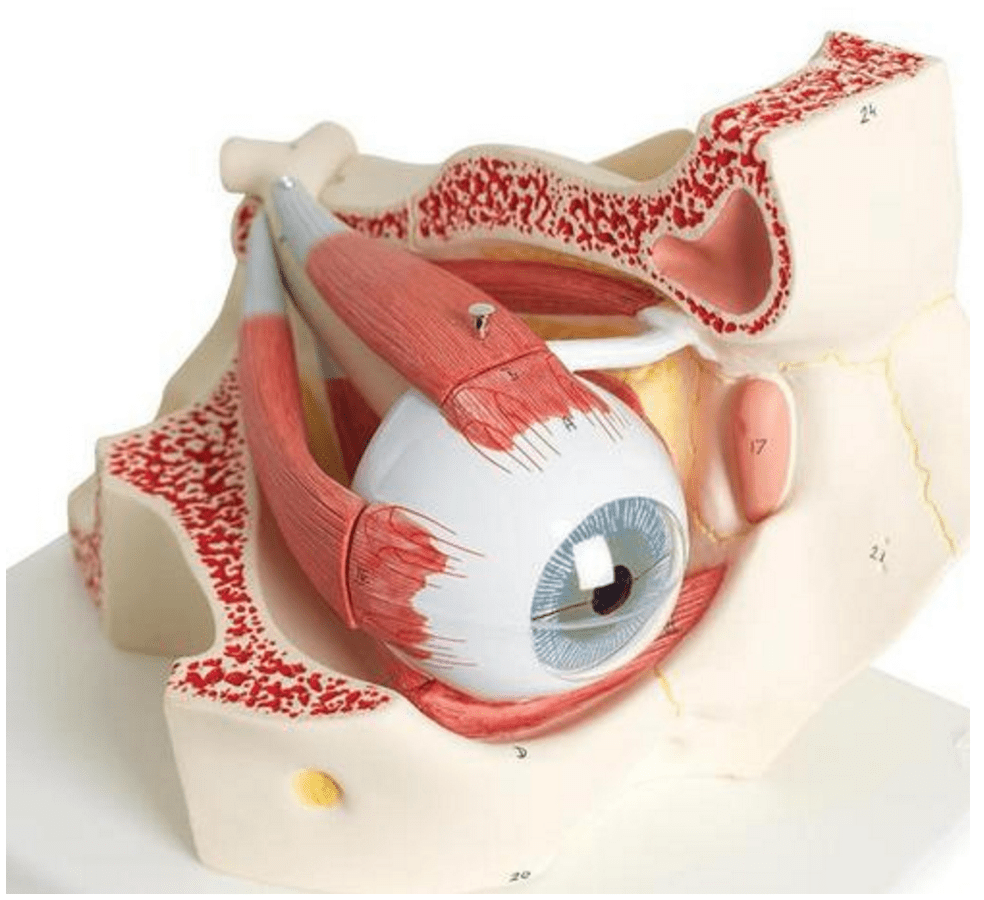

Selling anatomical models is the mainstay of eAnatomi, although we also spend a lot of resources developing our own anatomical materials such as posters. Anatomical models are used for various purposes and can show both defined tissues, organs and organ systems. Are you looking for a simple model of bone tissue or perhaps an advanced torso model based on MRI technology, you can find it all at eanatomi.com.